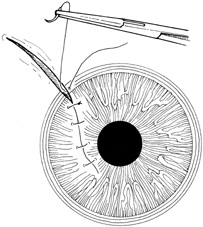

Tissue adhesive should be applied to a dry, deepithelialized bed. A capillary microapplicator or fine-gauge disposable needle is used to apply a very thin film of adhesive over the site (Fig. 3). Alternatively, adhesive may be applied using a sterile 2- to 4-mm polyethylene or silicone disc affixed to the end of an applicator stick with sterile ophthalmic ointment. The disc may be left in place or removed with care. Three to five minutes are required for polymerization of the adhesive. A bandage soft contact lens is applied for comfort and to prevent the glue from dislodging. While the contact lens is in place, a prophylactic antibiotic drop is administered. Over time, the tissue adhesive dislodges spontaneously as the wound surface reepithelializes. Alternatively, it may be gently removed with forceps after adequate stromal healing has occurred.